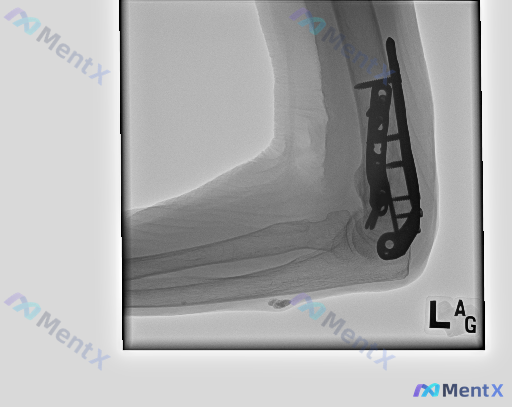

背景:左侧肱骨远端骨折术后,复查侧位X光片(标记“L”)。

- 肱骨远端可见金属接骨板+数枚螺钉内固定,钢板位置尚可,未见明显断裂/螺钉松动,可见骨愈合区域;

- 肱尺、肱桡关节对位尚可,关节间隙无明显异常;

- 重点:前臂近端腹侧(尺骨前方)软组织内,有一类圆形、边界相对清晰的孤立高密度影;

- 其余骨质未见明显破坏或疏松,关节腔内未见明显游离骨块。